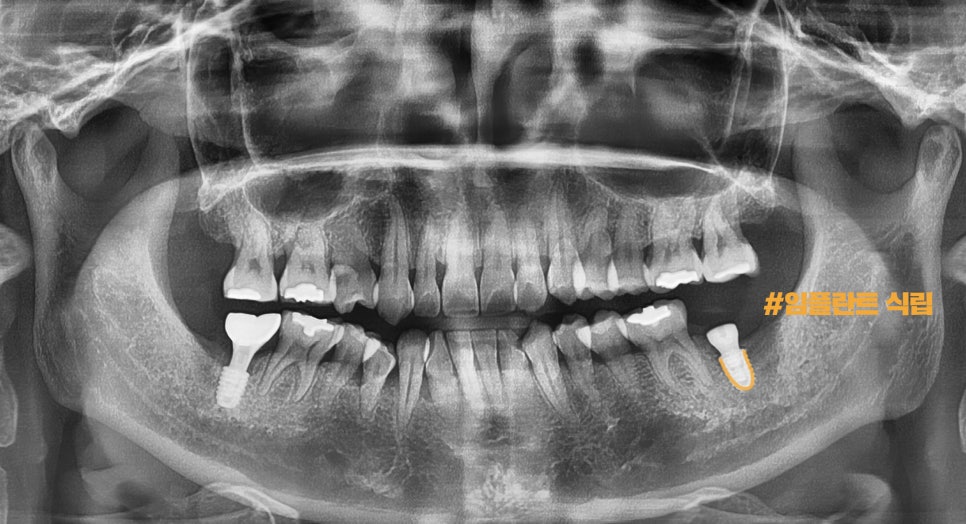

8개월 뒤)

환자께서

왼쪽 부위도 치료하고 싶어서

저희 병원을 다시 찾아오셨습니다.

마찬가지로

모의 수술을 통해서

픽스쳐가 심겨질 위치를 파악했으며,

이를 토대로

임플란트 수술을 진행한 다음

픽스쳐가 결합하는 기간을 갖게 되었습니다.

완성된 모습을 보여 드리겠습니다.

어금니 양쪽 모두

보철이 예쁘게 올라간 걸 볼 수 있으며,